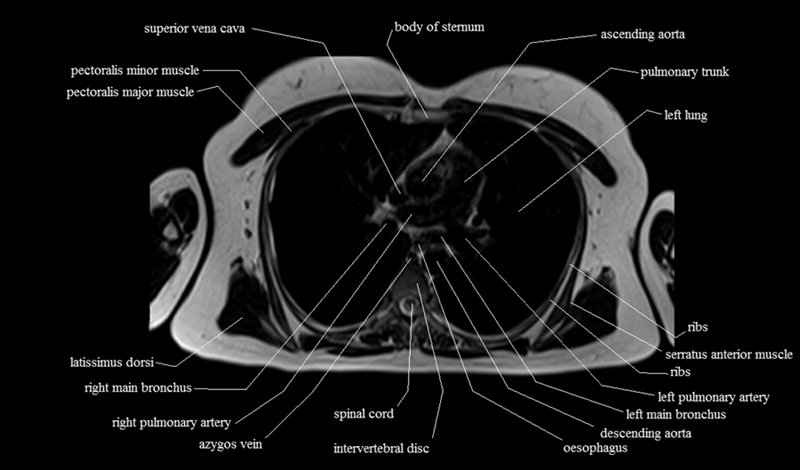

MRI Axial Cross Sectional Anatomy of Chest

This MRI chest (thorax) axial cross sectional anatomy tool is absolutely free to use. Use the mouse scroll wheel to move the images up and down, or alternatively, use the tiny arrows (→) on both sides of the image to navigate through the images. For a more detailed view, double-click the image to view it in full screen, and use the menu in the top right-hand corner to view individual slides or play them in a loop.